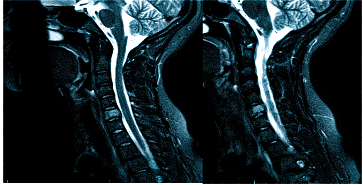

Если оно не дает необходимой картины по проблеме, то может быть назначена , а также: МРТ шейного отдела позвоночника

Важно! Если даже после подобной процедуры не станет ясна причина боли в голове, то потребуется дополнительная диагностика в виде МРТ, но уже позвоночника тела человека, а именно его шейного отдела.

Врач определяет не только вид обследования, но и его объем. Иногда требуется дать оценку не только структурам мозга, но и воротниковой зоны: голова может кружиться и болеть при шейном остеохондрозе, грыже, воспалении нерва и пр.